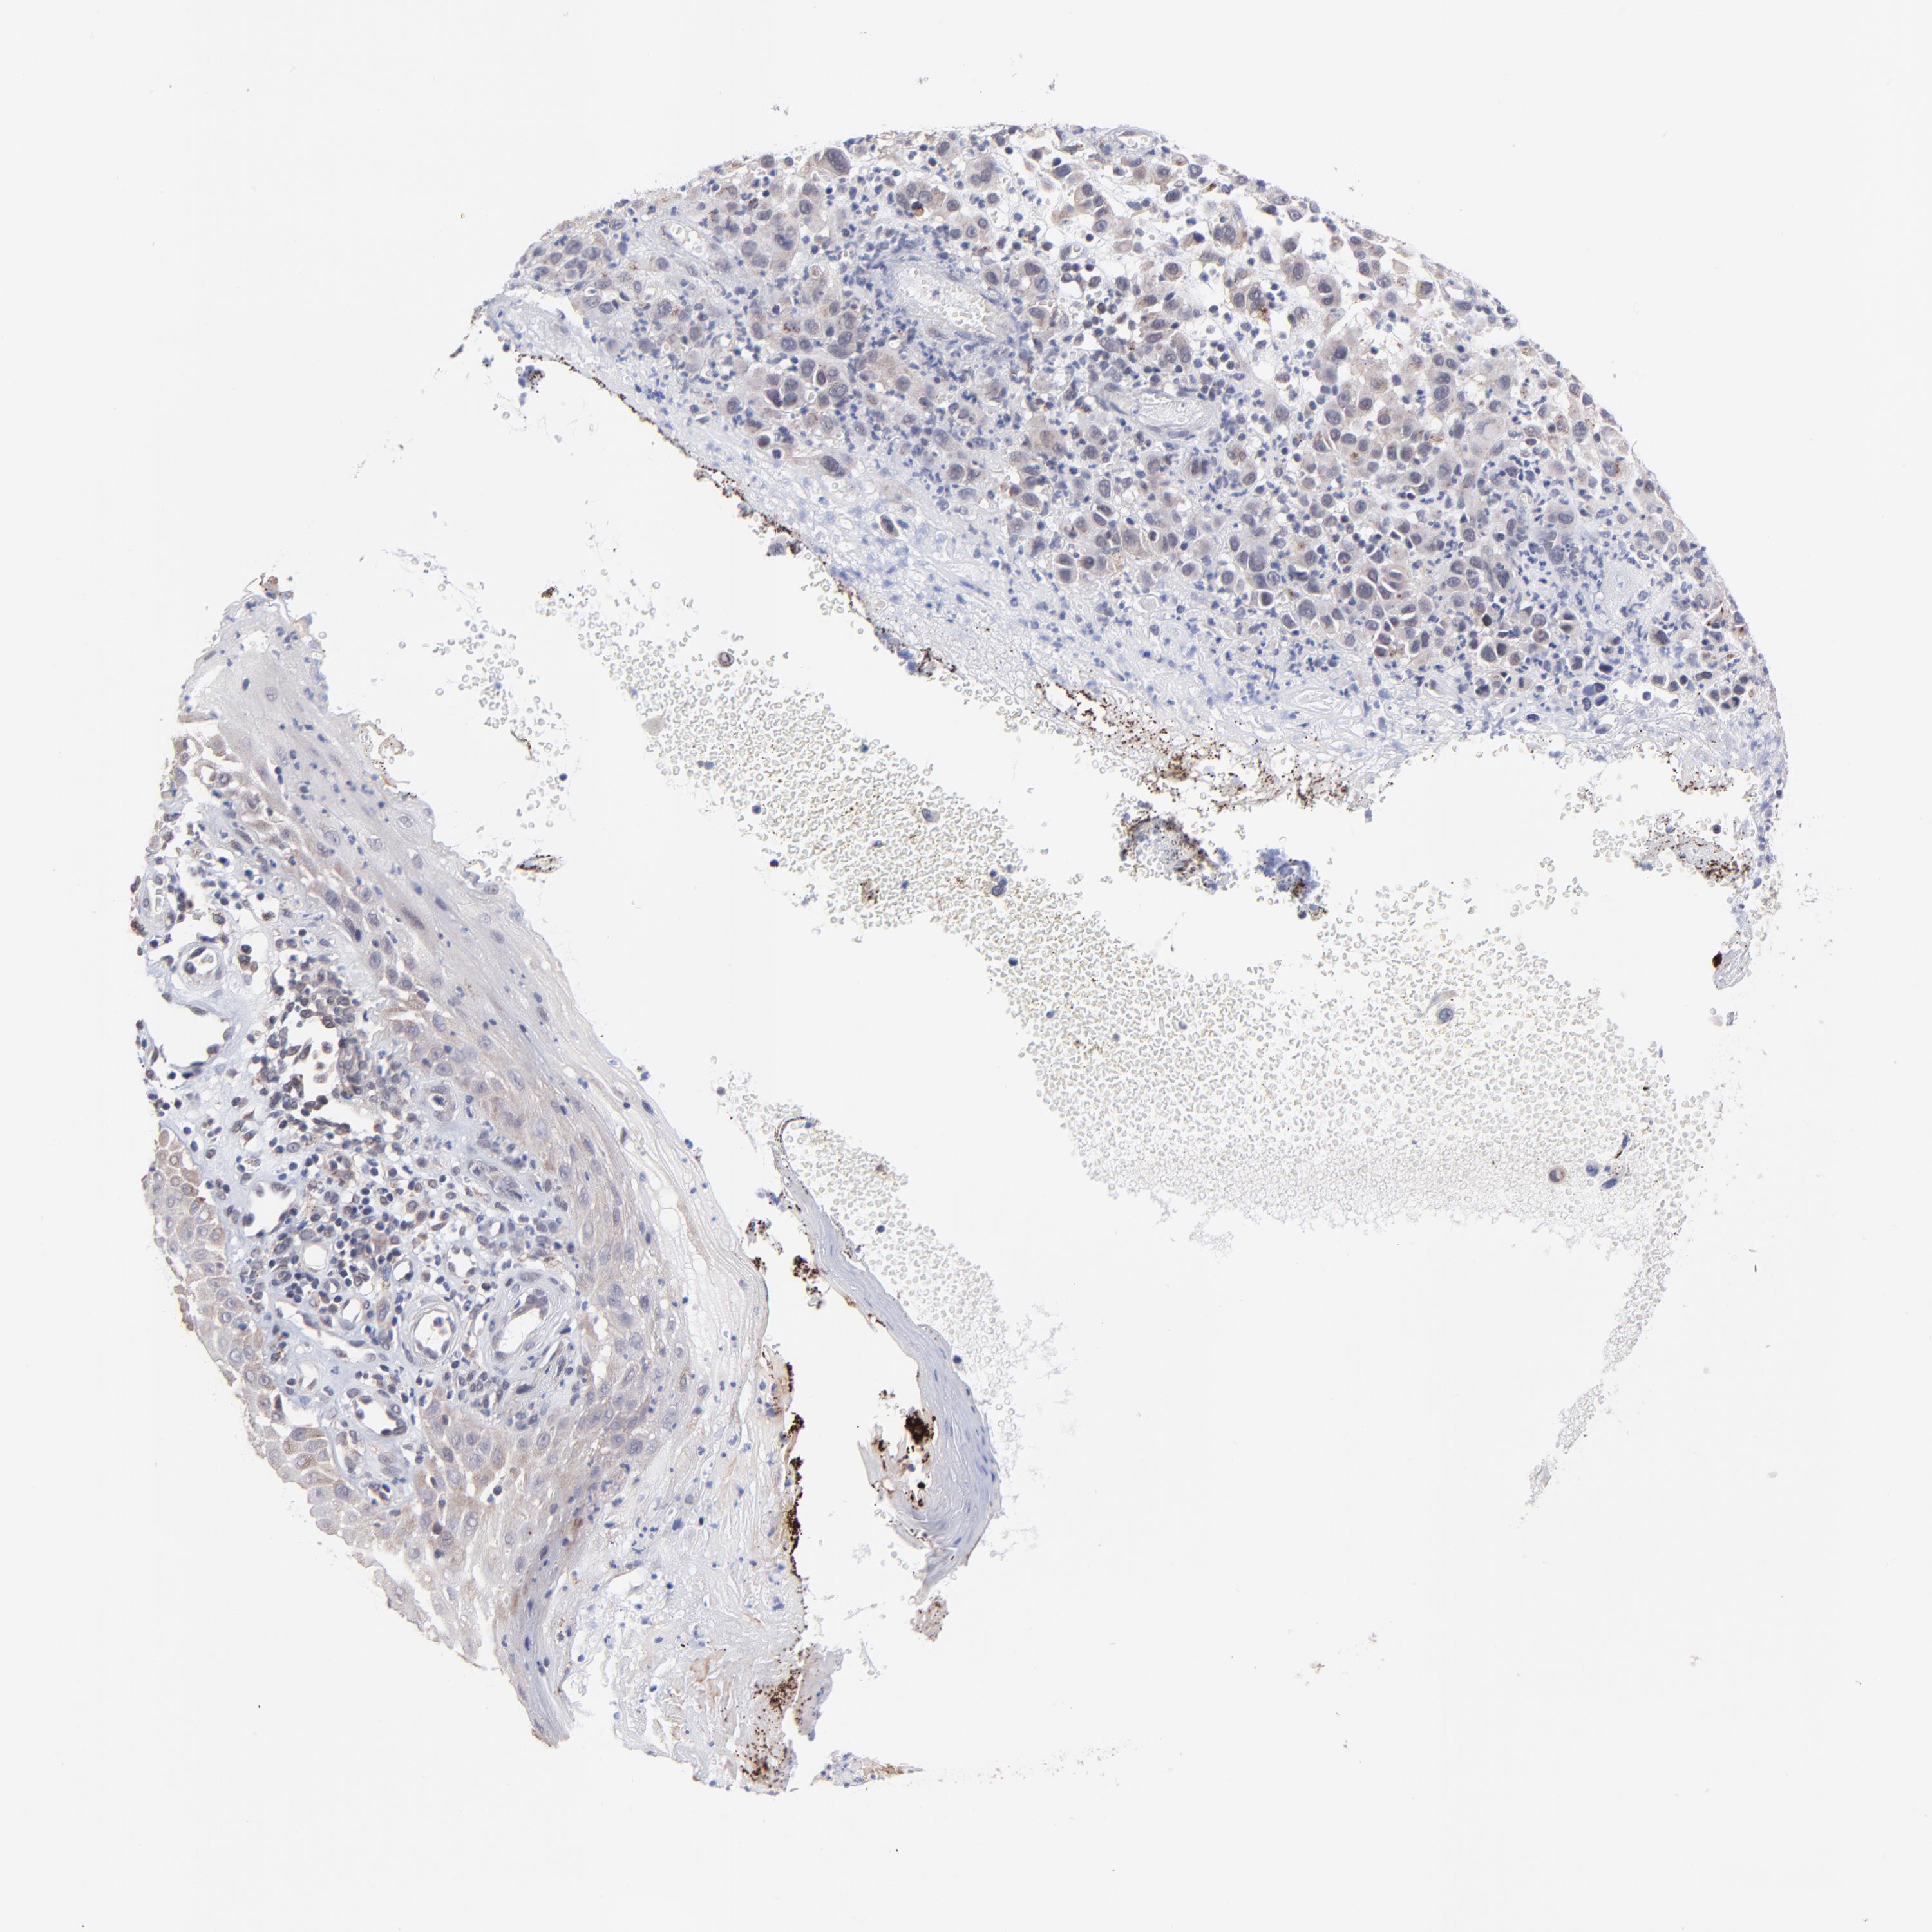

MELANOMA - Protein expressioni

A mouse-over function shows sample information and annotation data. Click on an image to view it in a full screen mode. Samples can be filtered based on level of antibody staining by selecting one or several of the following categories: high, medium, low and not detected. The assay and annotation is described here.

Note that samples used for immunohistochemistry by the Human Protein Atlas do not correspond to samples in the TCGA dataset.

Antibody stainingi

Antibody staining in the annotated cell types in the current human tissue is reported as not detected, low, medium, or high, based on conventional immunohistochemistry profiling in selected tissues. This score is based on the combination of the staining intensity and fraction of stained cells.

Each image is clickable and will lead to virtual microscopy that enables deeper exploration of all samples and also displays staining intensity scores, fraction scores and subcellular localization as well as patient and tissue information for each sample.

Antibody HPA003203

Staining

High

Medium

Low

Not detected

Intensity

Strong

Moderate

Weak

Negative

Quantity

>75%

75%-25%

<25%

None

Location

Nuclear

Cytoplasmic/membranous

Cytoplasmic/membranous,nuclear

Malignant melanoma, NOS

Malignant melanoma, Metastatic site